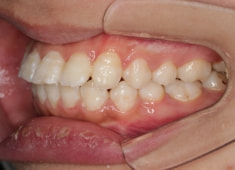

治療開始から5ヶ月後